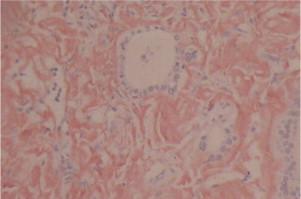

A 58-year-old male patient was diagnosed of Crohn's Disease (CD). He was admitted to our clinic with complaint of respiratory distress and rapid growth swelling in the neck. Ultrasound examination revealed huge multinodular goiter on both sides of thyroid gland. We performed bilateral total thyroidectomy. Pathological evaluation revealed AG.

一名58岁男性患者被诊断为克罗恩病(CD)。他因呼吸窘迫和颈部迅速增大的肿胀而入住我院。超声检查显示双侧甲状腺巨大多发结节性甲状腺肿。我们进行了双侧甲状腺全切除术。病理评估显示为AG。